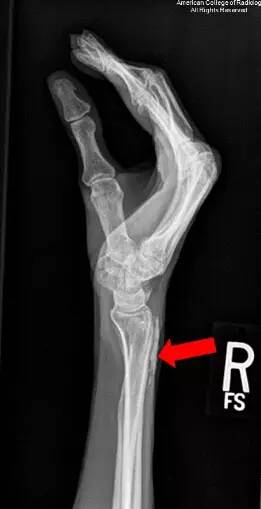

图 1 为右手侧位片示手腕背侧一分叶、线状钙化灶(红色箭头)。钙化未延伸至关节,也未见透明分隔